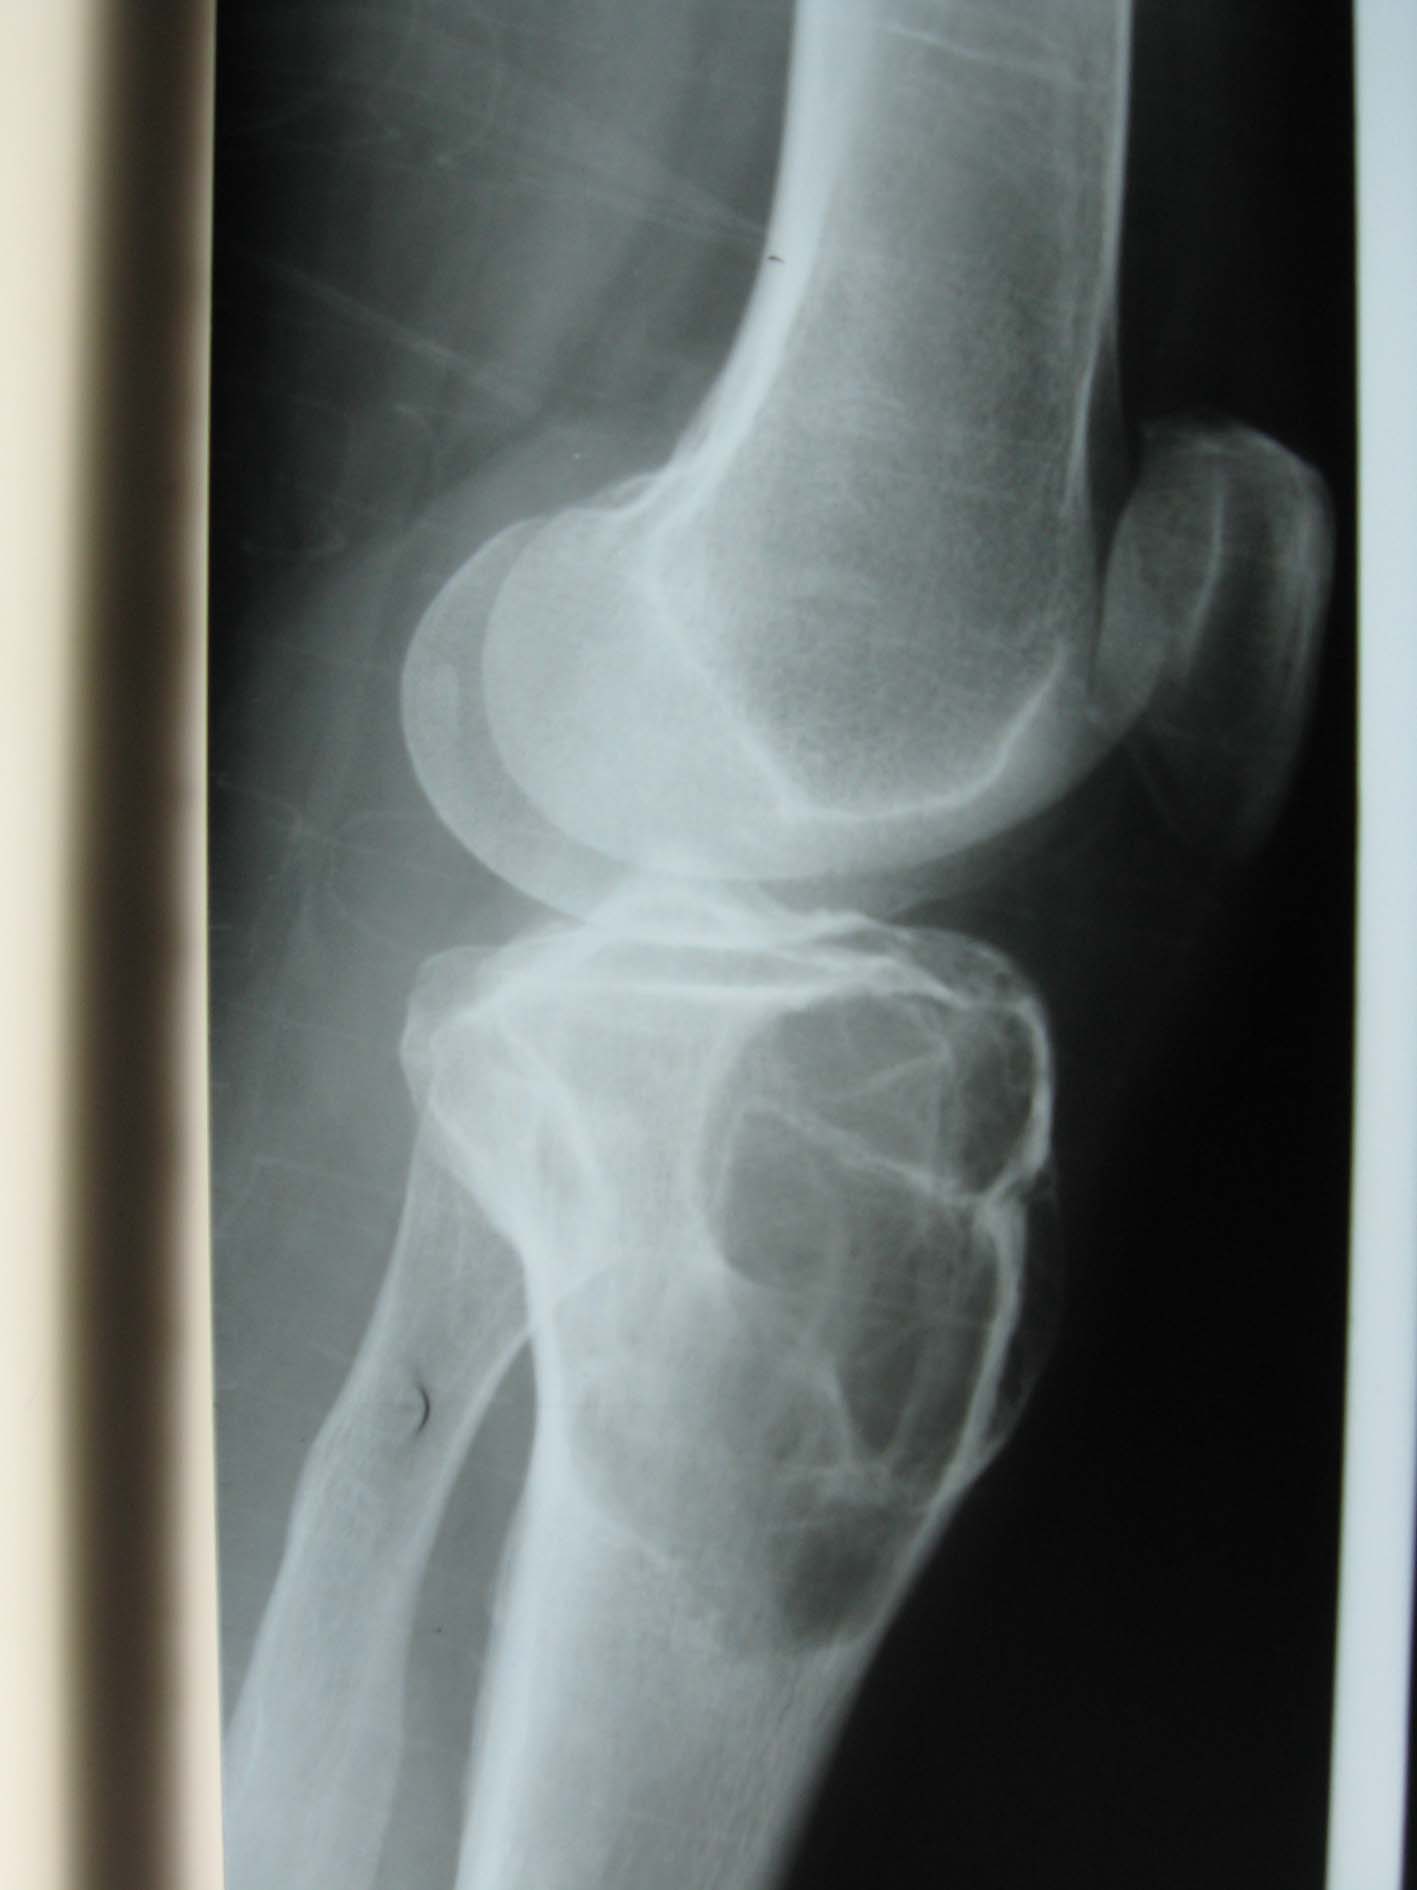

以下是引用流星1234在2009-3-9 22:19:00的发言:[br]胫骨骨端巨大囊性膨胀性溶骨破坏,与正常骨分界清楚,无硬化缘,其内有纤细间隔,呈皂泡状改变,支持骨巨细胞瘤.

以下是引用黑白光影在2009-3-9 22:59:00的发言:[br]本例患者膝关节可见胫骨髁间棘骨质增生变尖,髌骨后上缘亦有轻度增生改变,应为成年人。考虑胫骨上端骨巨细胞瘤可能性大。[br][br]骨巨细胞瘤:发病年龄较大,病变多位于长骨端有关节面下方,关节面常为肿瘤的部分轮廓。。由于肿瘤的纵行横行生长差不多,故肿瘤多呈球形。瘤内有皂泡状影。骨化及反应性骨硬化现象少见。而动脉瘤样骨囊肿发病年龄较轻,病变多位于干骺端,很少侵犯骨骺,常有不同程度的骨硬化现象。[br][br]鉴别诊断:[br]1、孤立性骨囊肿,多见于四肢,常为中心型,呈对称性轻度膨胀的骨破坏,周围为致密硬化带。囊壁外缘光滑整 齐,内缘则不光整。随骨骼生长逐渐移向骨干,常因病理性骨折而发现。[br]2、非骨化纤维瘤,常侵犯骨皮质,沿骨干蔓延,呈分叶状,边缘有硬化现象。有时边缘不完整,甚至有骨皮质断裂。[br]3、软骨粘液样纤维瘤,多见于青少年,偏心生长,分叶状,并呈分房样。突入软组织时多无包壳。破坏区内有斑点及斑片状钙化。[br]4、还有骨血管瘤、良性骨母细胞瘤,骨嗜酸性肉芽肿。[br][br][本贴已被 黑白光影 于 2009-3-9 23:00:25 修改过]